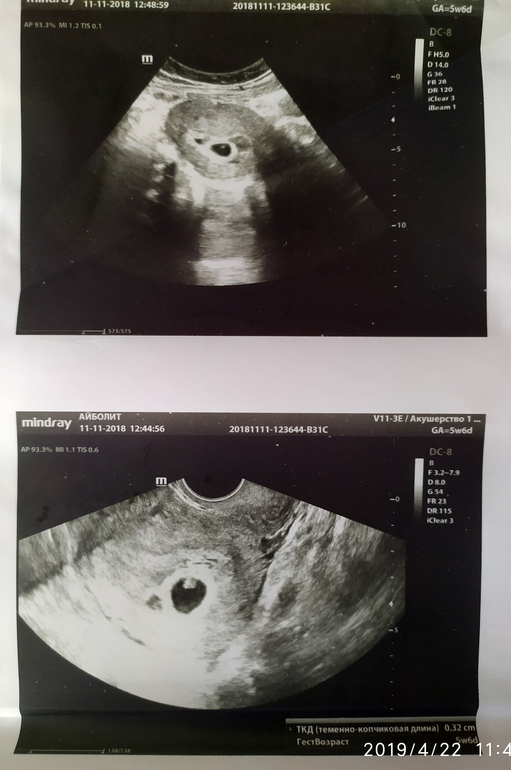

Вот снимок 2ПЯ в 5 недель 5 дней. При перемещении датчика контуры становились четкими. Который выше 15мм, который ниже 8мм. Может не стал специалист говорить "из благих побуждений", типа, чтоб не переживала, если маленькое ПЯ редуцируется. А, может, и правда, не ПЯ это вовсе(((

вот мои 2 пя для сравнения